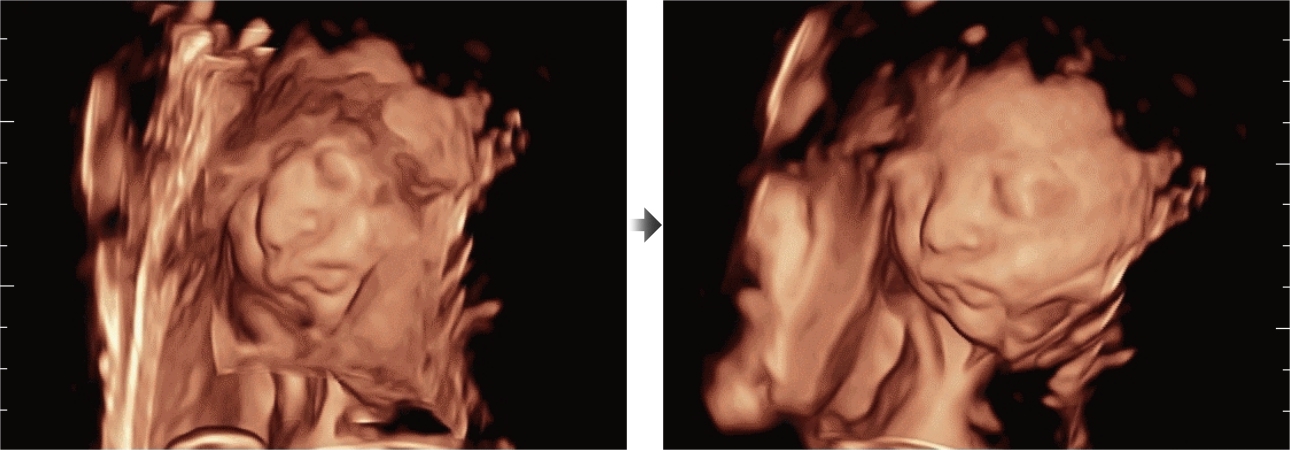

Assim como o n├Łvel de qualidade de imagem premium, o Resona 7 tamb├®m melhora as capacidades de investiga??o cl├Łnica com o revolucion├Īrio Fluxo V para avalia??o hemodin?mica vascular e a aquisi??o de plano mais inteligente do conjunto de dados 3D para diagn├│stico CNS fetal. Combinando a opera??o mais intuitiva baseada em gesto de multi-toques e todos os recursos cl├Łnicos essenciais, Resona 7 est├Ī realmente conduzindo novas ondas na inova??o de ultra-som.